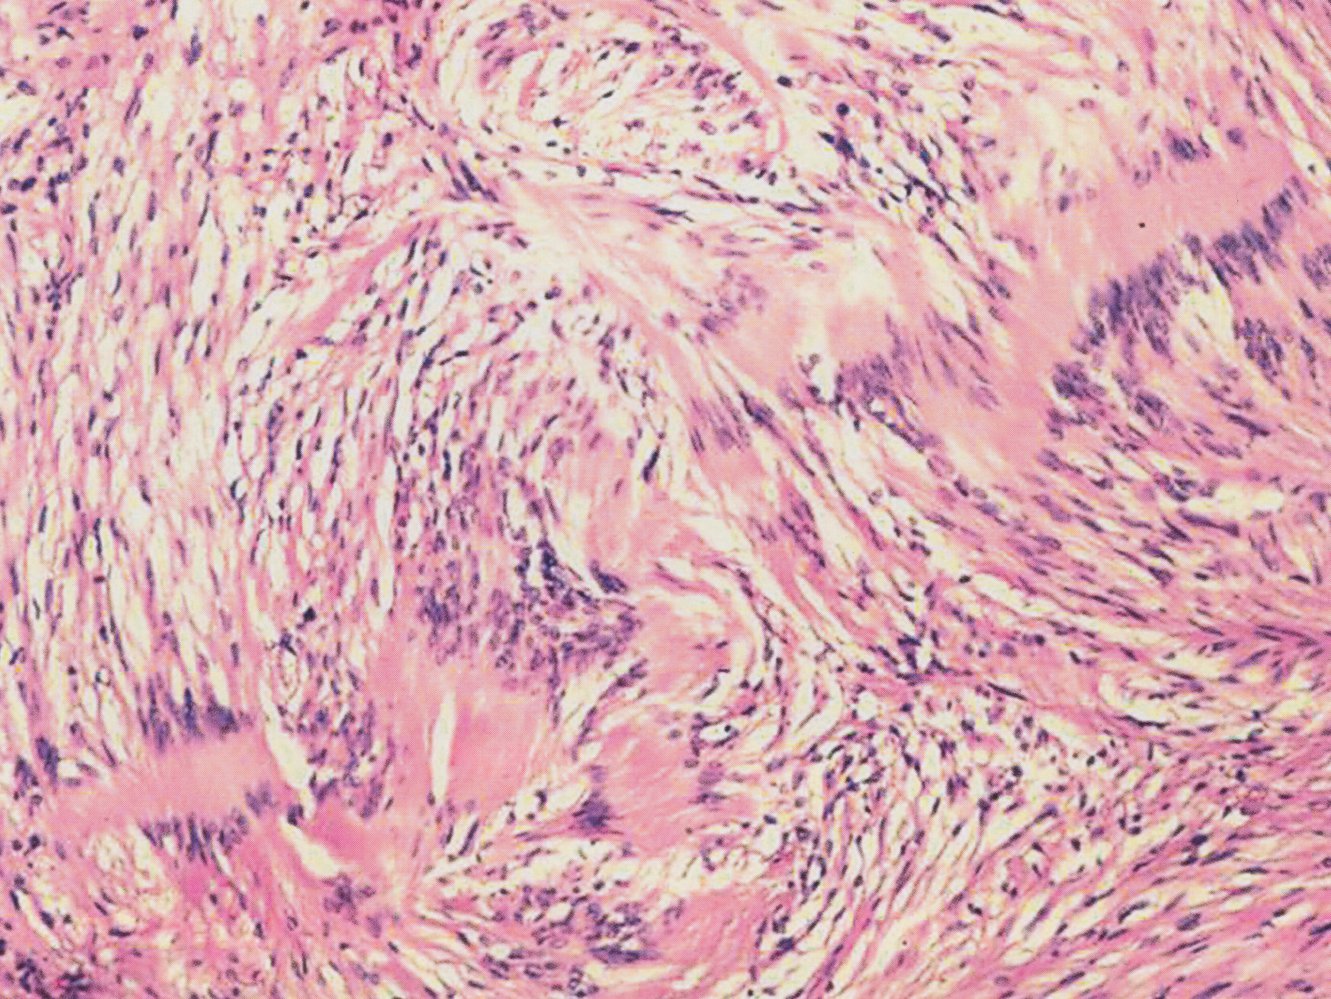

• Microscopic findings

• Spindle cells in palisades (Antoni A tissue) alternating with myxoid hypocellular areas (Antoni B tissue)

• S-100 positive